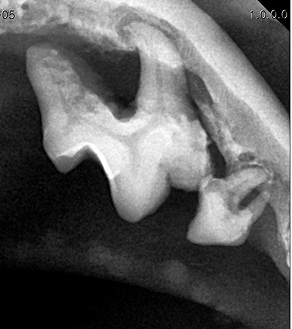

BEFORE

AFTER